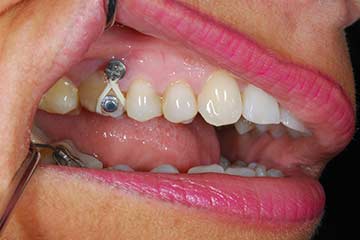

Trattamento ortodontico nell'adulto con intrusione del I° molare superiore mediante l'utilizzo di mini impianti

Impianto post-estrattivo